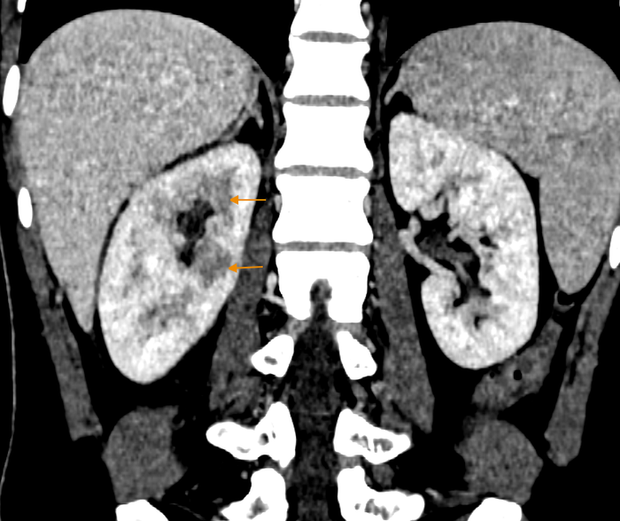

Kết quả các xét nghiệm và khám lâm sàng cho thấy chỉ số viêm của bệnh nhân tăng, hình ảnh CT phát hiện dịch tụ xung quanh thận, mô thận không đồng đều, đặc biệt ở vùng sau bể thận. Bác sĩ chẩn đoán bệnh nhân mắc viêm thận bể thận cấp tính và yêu cầu nhập viện để điều trị nội trú ngay lập tức.

Hình ảnh CT của bệnh nhân cho thấy sự phân bố không đồng đều của nhu mô thận và hiện tượng viêm nhiễm thể thận (Ảnh: BSCC)